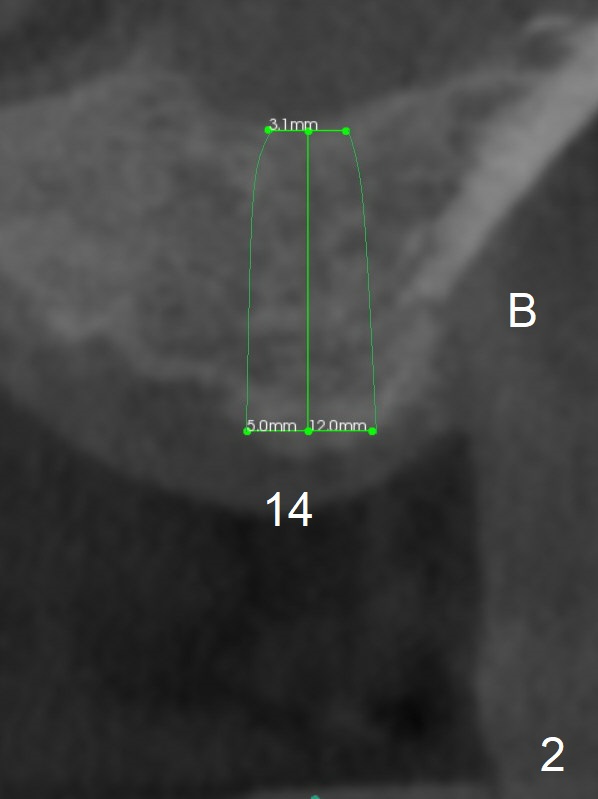

Narrow Mesiodistal Space

A 57-year-old man will return for #14,15 implant placement. The mesiodistal space is narrow (Fig.1: 16.8 mm vs. ~20 mm), whereas the buccopalatal dimension is wide (Fig.2,3 (B: buccal)). The diameters of the 2 implants will be determined by the former parameter. Bone density at the sites are 100-400 units. It is easy for bone expansion/condensation when bone density is 100-200 units.